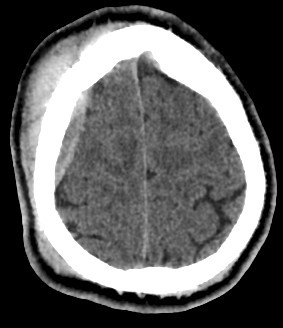

brain CT scan

A brain CT scan, also known as a computed tomography scan or CAT scan, is a non-invasive imaging procedure that uses X-rays to create detailed cross-sectional images of the brain and surrounding structures. It's a common diagnostic tool for evaluating head injuries, strokes, brain tumors, and other neurological conditions. Here's a more detailed explanation: What it is: A brain CT scan uses a series of X-ray beams that rotate around the head, capturing multiple images from different angles. These images are then processed by a computer to create detailed cross-sectional views of the brain, allowing doctors to visualize the brain's structures and identify any abnormalities. The scan can be performed with or without contrast dye, which helps to highlight certain tissues and blood vessels for better visualization. Why it's used: Traumatic brain injuries: CT scans are often the first imaging test used to assess the extent of head injuries and identify potential fractures, bleeding, or swelling. Stroke: CT scans can quickly identify whether a stroke is caused by a blood clot (ischemic stroke) or bleeding (hemorrhagic stroke), guiding appropriate treatment. Brain tumors: CT scans can help detect and assess the size and location of brain tumors. Other neurological conditions: CT scans can also be used to diagnose conditions like hydrocephalus (excess fluid in the brain), aneurysms (bulges in blood vessels), and certain types of dementia. Guiding procedures: CT scans can be used to guide biopsies or other procedures involving the brain. What to expect during the procedure: You will lie on a table that slides into the CT scanner, which is a large, doughnut-shaped machine. The scan itself is painless, but some people may experience slight discomfort from lying still on the hard table. If contrast is used, you may feel a warm or flushing sensation, or a metallic taste in your mouth. The scan typically takes only a few minutes. Risks and Precautions: CT scans involve exposure to radiation, but the risk from a single scan is generally considered low. If you are pregnant, it's important to inform your doctor, as alternative imaging methods may be considered to avoid exposing the fetus to radiation. If you have any allergies, particularly to contrast dye, make sure to inform your doctor.